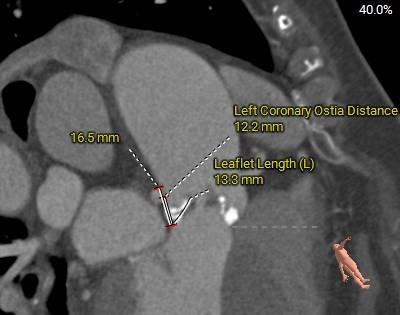

瓣环角度及弓角弓距

◇ 主动脉瓣环水平夹角52°,非横位心,主动脉弓角度较锐(43°)及弓距偏短;